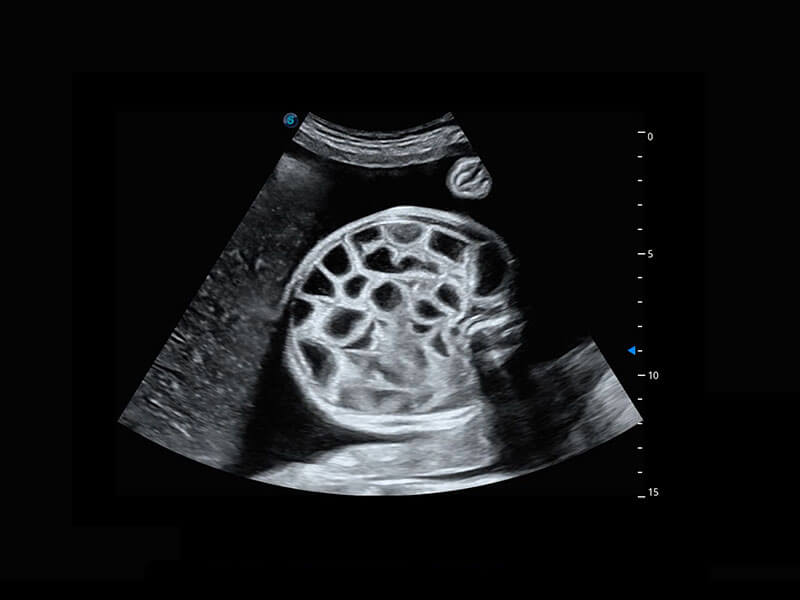

高分辨率容积成像-早孕胎儿

胎儿体循环